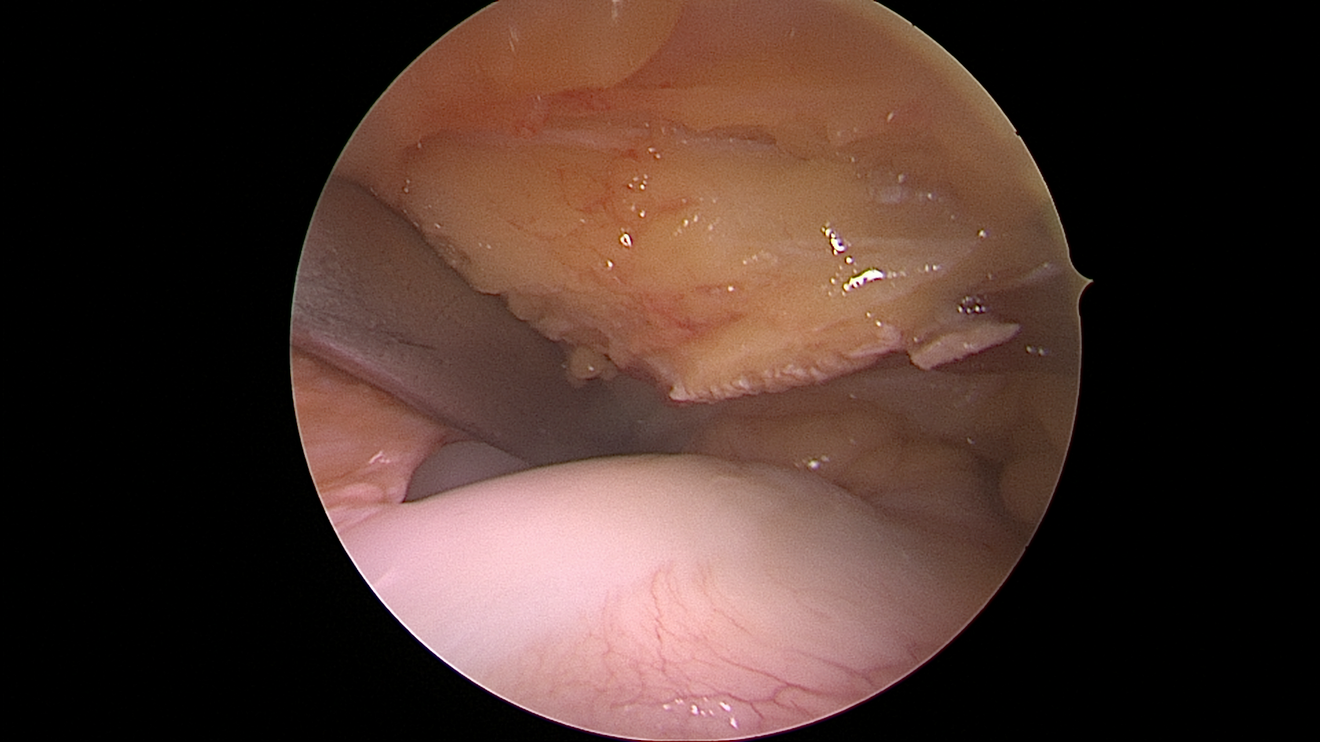

Die arthroskopisch assistierte Frakturversorgung (insbesondere am Tibiakopf) im Rahmen von Band- bzw. Kombinationsverletzungen ist ebenfalls ein Schwerpunkt der Abteilung. Der ärztliche Direktor PD Dr. med. Schlumberger ist im DKG-Komitee „Frakturen“ vertreten.

Meniskus

Der Meniskus fungiert als „Stoßdämpfer“ zwischen Oberschenkel und Unterschenkel, verbessert die Kongruenz der Gelenkpartner und trägt zusätzlich zur Stabilität des Kniegelenkes bei. Je nach Rissform, Patientenalter, traumatischer oder degenerativer Ursache bestehen unterschiedliche Behandlungsoptionen von konservativer Therapie bis hin zur operativen Versorgung mittels Teilresektion oder Meniskusnaht. Bei speziellen Meniskusverletzungen (z.B. der sogenannten Wurzel-Läsion) kann – um den Einheilungsprozess zu gewährleisten – auch ein Zusatzeingriff wie eine Umstellungsosteotomie bei O-Beinen nötig werden.

Als Behandlungsmöglichkeiten für Knorpelschäden gibt es die sog. Abrasionschondroplastik / Mikrofrakturierung, bei der der defekte Knorpel bis auf den Knochen abgetragen und dieser dann mit kleinen Löchern perforiert und ggf. mit einer speziellen Membran bedeckt wird. Durch die Perforationen tritt Knochenmark in den Defekt ein und es bildet sich ein sog. Regeneratknorpel. Auch die Möglichkeit einer Knorpelzelltransplantation (sog. „ACT“) wird bei uns angeboten. Hier werden in einer ersten Operation Knorpelzellen entnommen und in einer zweiten Operation in den Defekt eingebracht (entweder als sog. ACT Inject in einer Suspension oder als ACT 3d auf einer Membran). Auch die körpereigene Transplantation eines Knochen-Knorpel-Zylinders (OATS / Mosaikplastik) ist eine Therapiemöglichkeit, die wir anbieten können.